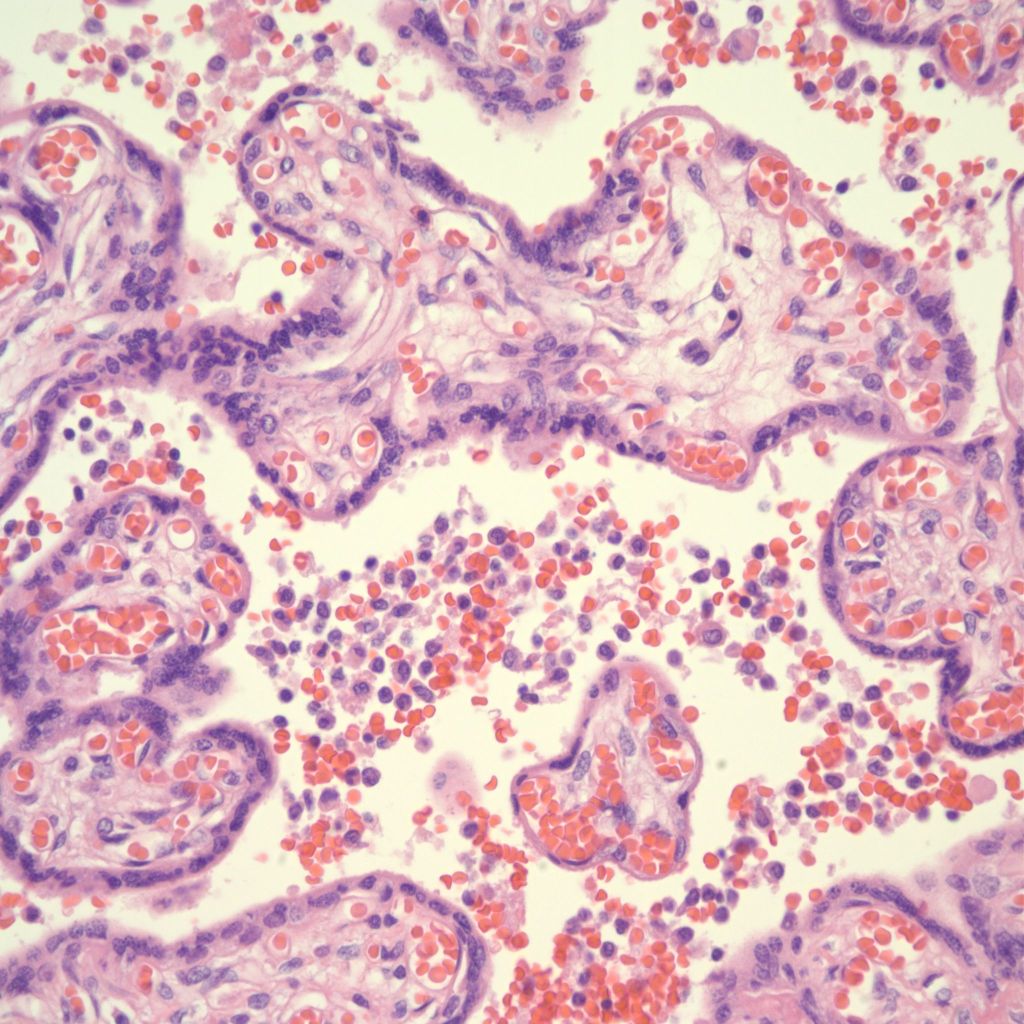

Microscopic criteria: The primary criterion is monocytes clustered in the intervillous space which can be confirmed by CD 6810,17. The monocytes often have kidney bean shaped nuclei and prominent cytoplasm. Some other consensus criteria are that the inflammatory cells in the intervillous space should be at least 80% monocytes, and these should be maternal cells1,17.

High Grade (massive) CHIV

Low Grade CHIV (5-50% of the intervillous space occupied by monocytes)

There is a focus of intervillous fibrinoid with no definite cytotrophoblast that is not re-covered with syncytium suggestive of recent syncytial injury (F). (10x, H&E)